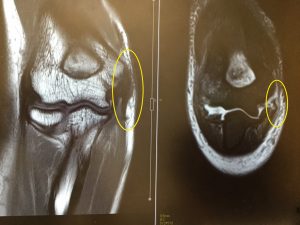

右が3年前、受傷直後のMRI画像で、丸で囲んだ部分の黒いくの字状に見えるのが、切れた内側側副靭帯を含む組織です

左が昨日撮った手術後、3年経過した画像です

その黒い帯状の線が、しっかり上腕骨に向かって伸びています

断裂した靱帯を手術で縫合したのですから、当然と言えば当然ですが、改めてこうして画像で比較すると、回復したんだなぁ、と実感